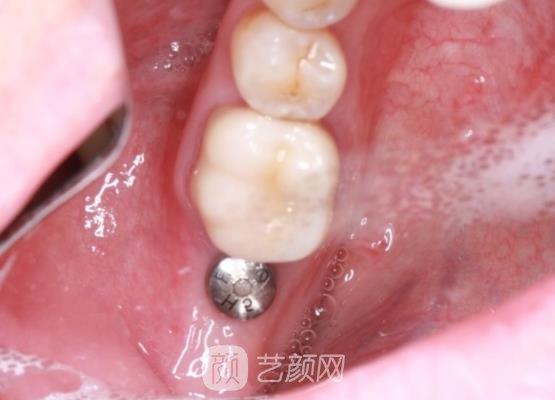

种植牙案例展示:

我喜欢那种人机坚固的牙齿,我觉得那种牙齿会看上去更加的美观,而且也会让整个人在吃东西的时候变得更加的便捷,可是不知道为什么我好像没有那么幸运,有一次在和朋友打闹的时候,却让我的牙齿磕掉了一颗,当时看到牙齿脱落的时候,我整个人感觉都要崩溃了。

所以有那么段时间我的心情一直都不是很好,几乎都没有和朋友一块出去聚会,而且每天都是将自己锁在屋里边的,不愿意和人交流,有时候想到自己喜欢的食物都不愿意去尝试,因为实在是太不方便,后来有一次我的好朋友跟我说,让我可以去医院做一下检查。

因为他帮我在网络上看了一下,现在医院里面是可以做种植牙手术的,通过这个手术能够让我的牙齿还原到以前的样子,其实刚开始听他这样说,我是不太相信,我觉得不可能有这么好的事情会降临到我的头上。

但是为了能够让自己的牙齿长出来,我还是决定去医院尝试一下,在那天我正好给自己安排了一下时间,我就来到了这家医院,在调节手术之前我们和医生也沟通了好长时间,我把我个人心里是怎么想的都告诉了一下医生,医生都很了解我的一些情况。

之后就为我安排了手术的时间,很快就开始做手术了,整个手术在调节的过程中其实都是比较轻松的,也没有我想象中的那么害怕,而且整个手术下来也用了没有多长时间,在完成手术之后,我还在医院观察了几分钟,了解了手术的一些术后相关护理工作。

在了解了情况之后就回家了,在后续的一段时间其实恢复的都挺不错的,就是在刚刚做完手术之后,可能是因为刚种植了牙齿吧,有一些不太适应,觉得牙齿有一些东西,不过也不太严重,我是可以承受的。

手术大概用了四五个月的时间吧,我的调节部位就已经恢复了,而且看到牙齿恢复的这么坚固整齐,其实我的心里真的是挺开心的,没有想到医美整形行业竟然发展的这么迅速,让我在短短的时间之内竟然有了这么大的变化,心情真的太好了。